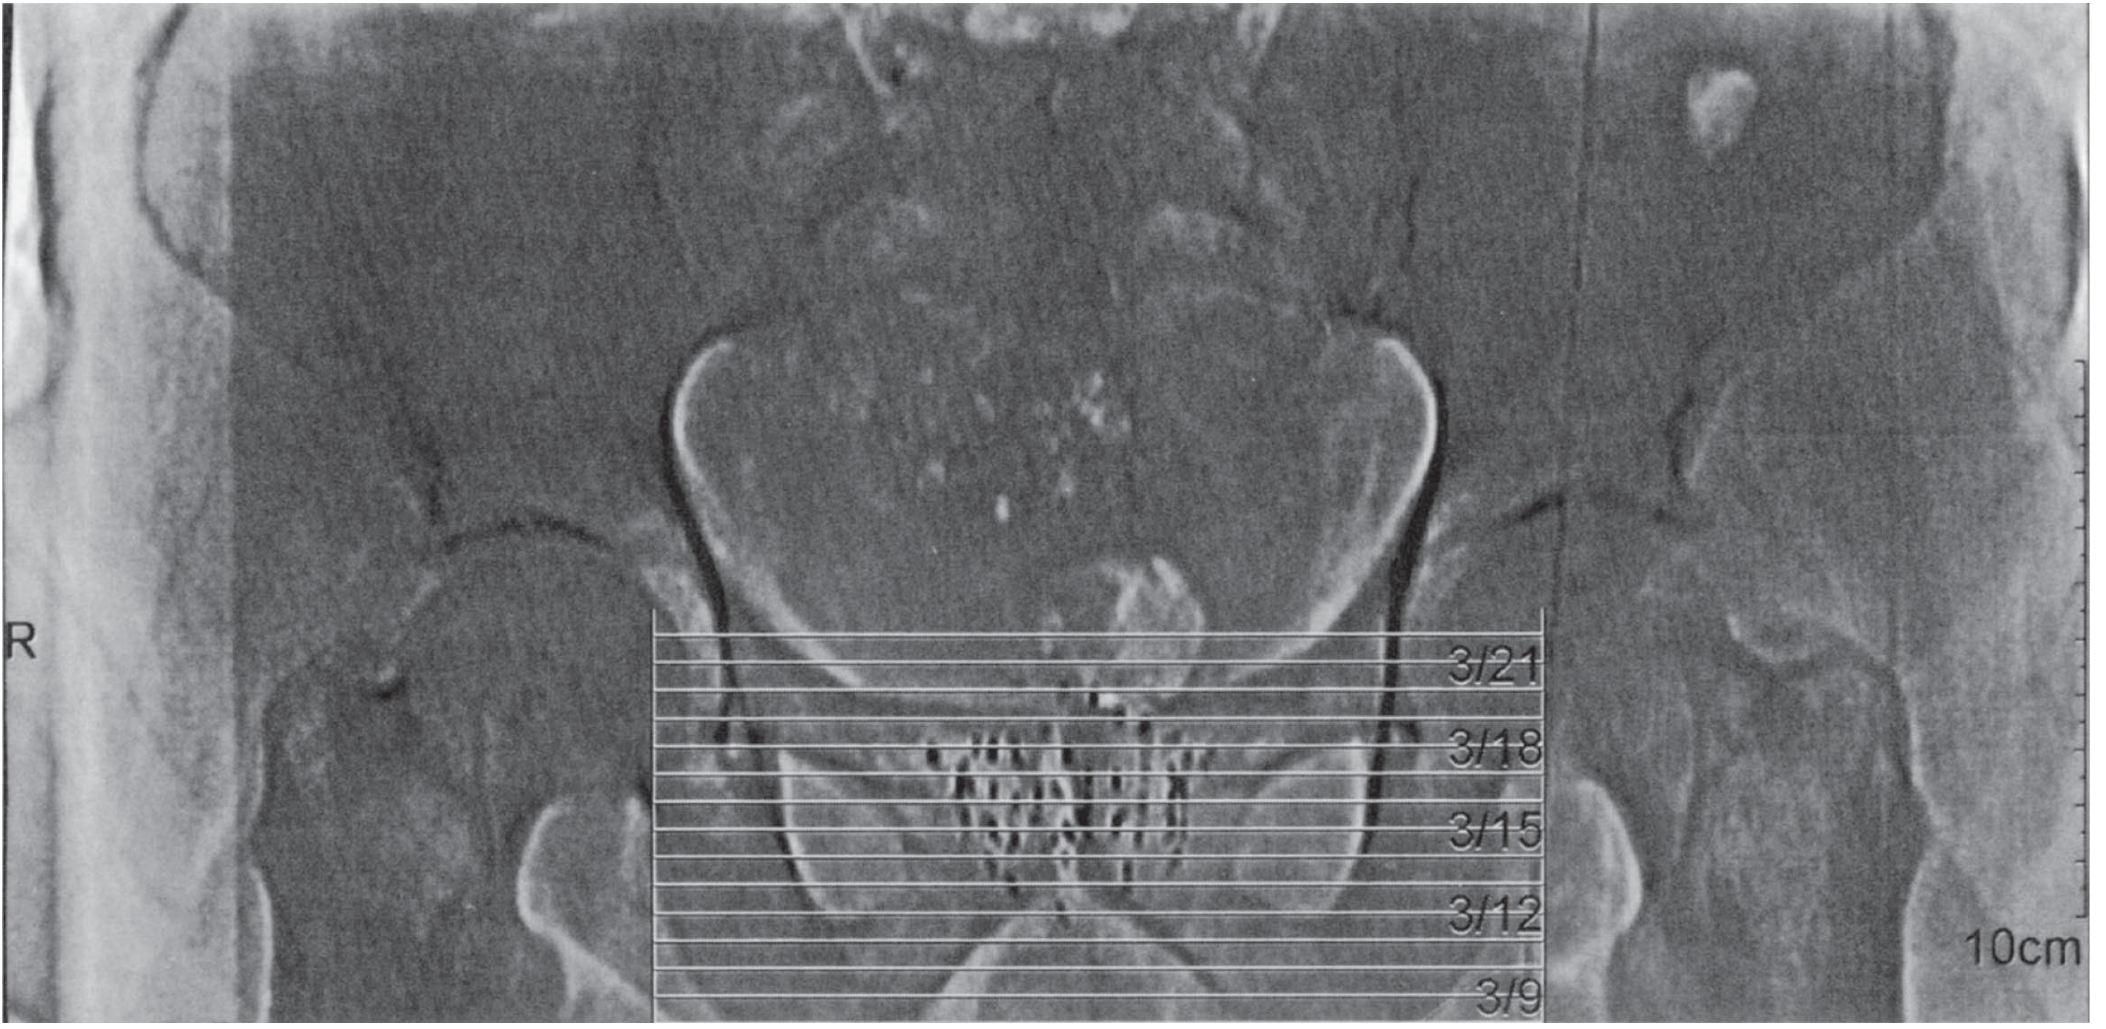

Ultrasound-guided permanent interstitial brachytherapy implant of the prostate, showing needle grid placement

Ultrasound-guided permanent interstitial brachytherapy of the prostate — Smith and Tanagho's General Urology, 19th Ed.

• LDR seed implant: ¹²⁵I or ¹⁰³Pd seeds implanted transperineally under transrectal ultrasound (TRUS) guidance. Used for low-to-intermediate risk disease.